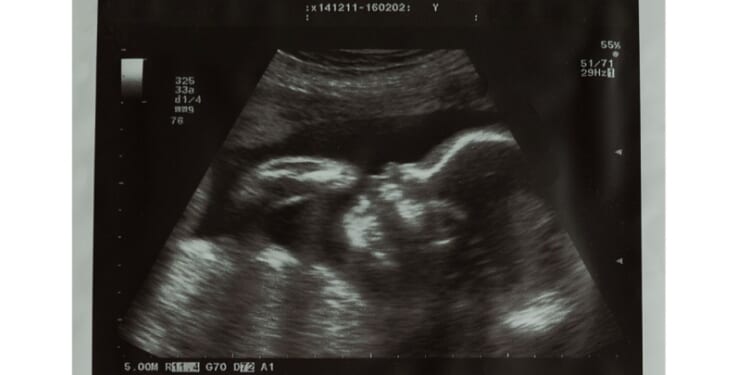

RightNow co-founder Alissa Golob was 22 weeks’ (five months’) pregnant when she went into Cabbagetown Women’s Clinic in Toronto. “No reason was given for wanting a late-term abortion,” the video emphasized. “And no reason was asked.”

In fact, at 22 weeks a baby in the womb begins to become familiar with voices; her brain is rapidly developing, and she can feel touch. The baby can also feel pain at this point.